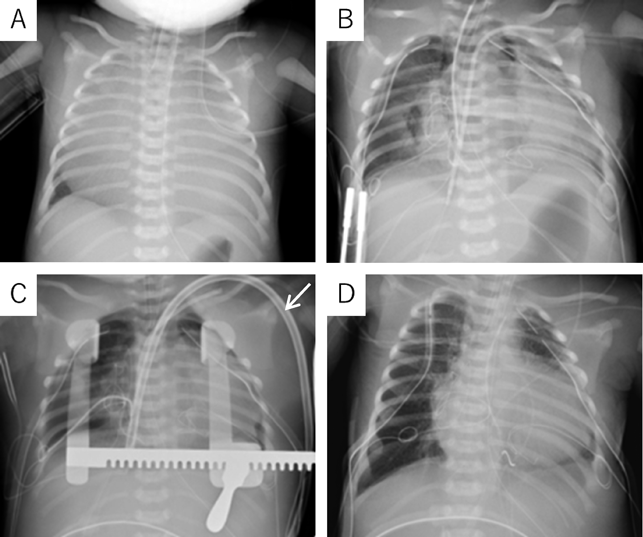

A 39-year-old gravida (gravida 3, para 0) was referred to our hospital at 24 weeks’ gestation for the perinatal care of her fetus diagnosed as having severe tricuspid valve regurgitation. A fetal echocardiography revealed severe tricuspid regurgitation, anatomically atretic pulmonary valve, and ductus arteriosus with retrograde blood flow. The tricuspid valve was severely dysplastic and thickened without typical plastering, with its diameter of 8.9 mm (z-score: 1.31). Pericardial effusion was noted. The cardiothoracic area ratio (CTAR) and Celemajer index2) were 0.46 and 0.9, respectively. After 33 weeks’ gestation, the right atrium and the right ventricle gradually dilated. The right ventricle was thin, and the left ventricle was banana-shaped. At 36 weeks’ gestation, her CTAR and Celemajer index increased to 0.68 and 1.6, respectively (Fig. 1). The tricuspid valve annular diameter was 17.0 mm (Z-score: 1.94) and the tricuspid regurgitation jet peak velocity was 2.3 m/s. The Great Ormond Street Echocardiography (GOSE) score,5) Simpson Andrews Sharland (SAS) score,6) and Tricuspid malformation Prognosis Prediction (TRIPP) score7) were IV, 7, and 5, respectively. The predicted mortality rate from the GOSE score was 100%, the SAS score also predicted high mortality, and the TRIPP score was borderline.5–7) Based on these fetal echocardiographic findings, we predicted that the baby would be in a critical condition after birth due to severe tricuspid regurgitation and pulmonary insufficiency. Therefore, we planned an elective cesarean section and prepared for early cardiac surgery.

Fig. 1 The fetal echocardiography at 36 weeks’ gestation. (A) The right atrium is markedly enlarged. The cardiothoracic area ratio and Celemajer index were 0.68, and 1.6, respectively. (B) Severe tricuspid valve regurgitation.

L, lung; LV, left ventricle; RA, right atrium; RV, right ventricle

At 37 weeks 5 days’ gestation, a 2,756 g female baby was delivered via elective cesarean section. Artificial ventilation was begun, and prostaglandin was administered. Saturation of percutaneous oxygen (SpO2) increased from 20% to 50%. Apgar scores were 2 and 2 at 1 and 5 minutes after birth, respectively. A chest radiograph showed severe cardiomegaly and a cardiothoracic ratio of 98% (Fig. 2). An echocardiography confirmed the prenatal diagnosis and showed massive tricuspid regurgitation. She continued to be hypoxic with SpO2 at 50% after intubation. Within 92 minutes after birth, surgery was initiated using cardiopulmonary bypass with an arterial cannula into the ascending aorta and bi-caval venous cannulae. The ductus arteriosus was ligated, and the tricuspid valve annulus was closed using a 0.4 mm expanded polytetrafluoroethylene patch with a 3 mm-diameter hole. The atrial septum and the dilated right atrial wall were excised widely. After aortic unclamping, the right ventricular wall was plicated longitudinally using 3-0 braids (Nespolene®, Alfresa, Osaka, Japan). An aorto-pulmonary shunt was constructed, using a 3.0 mm-diameter expanded polytetrafluoroethylene tube graft, between the brachiocephalic artery and the right pulmonary artery. During weaning from cardiopulmonary bypass, hypoxia and hypoventilation were observed. Therefore, HFV (fraction of inspired oxygen (FiO2), 100%) with inhaled nitric oxide (iNO) 20 ppm was used to successfully wean from cardiopulmonary bypass. The patient was returned to the intensive care unit with her chest open.